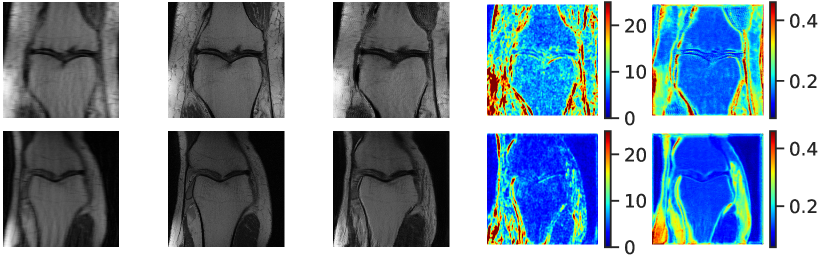

4.5 Uncertainty Scores

Additional to improved accuracy we demonstrate the efficacy of estimating the scale maps with the proposed method. The input-dependent non-negative scale maps are derived from the second output branch , see (9). Indeed, the predicted scale maps are able to model uncertainty inherent from data. This can be observed in Figure 8, where in addition to the transferred images also the predicted scale maps and the absolute residuals between predicted and ground truth images are displayed. Obviously, uncertainty is relatively greater in regions with higher residual values. From the scale maps it can be deduced for which positions the generator is comparatively uncertain in its prediction, such as the cerebral cortex and eye sockets in head MRI or the lateral knee ligaments in knee MRI.

[.52]

[.44]

The correspondence between residual and scale maps suggests that the latter can be used as an approximation to a prediction’s residuals that are not available due to the lack of ground truth data in unsupervised learning. In order to quantitatively study this relationship we visualize mean absolute residual score and mean uncertainty maps for 512 randomly selected unseen test images in a scatter plot (see Figure 8). Moreover, we compare our uni-directional method UAPI also to the relations observed by UGAC that models uncertainty with the help of a bi-directional cycleGAN [9]. For modality propagation as well as accelerated MRI enhancement we visually observe an approximate positive linear correlation between mean absolute residual scores and mean uncertainty scores. We calculate the Pearson correlation coefficient (PCC) to obtain a quality estimate for the linear correlation and compare between UAPI and UGAC. Our method returns a slightly higher PCC on IXI (UAPI: 0.69, UGAC: 0.67). The discrepancy between both methods even increases on FastMRI (UAPI: 0.72, UGAC: 0.45). This further encourages the idea that scale maps derived from our approach can be used to indicate the overall quality of a transferred image.